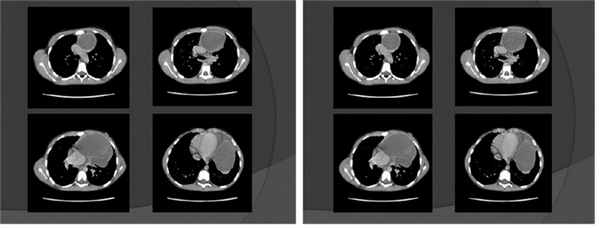

КТ органов грудной клетки — картина кистозного образования средостения слева. Небольшой объем жидкости в плевральной полости слева и в перикарде ( рис. 2 ).

Рис. 2. Компьютерная томограмма грудной клетки девочки Т., 9 лет. Иллюстрация М.Ю. Петрова, заведующего отделением, врача-рентгенолога ГАУЗ АО «Амурская областная детская клиническая больница»